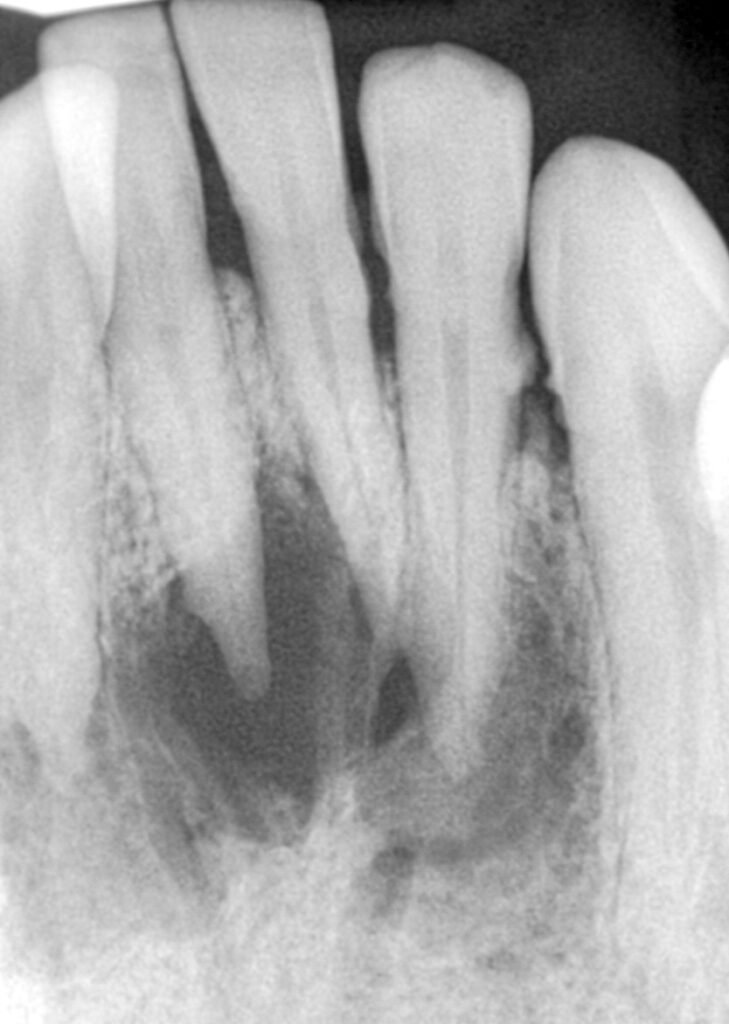

Évolution clinique en 3 phases

Phase de latence :

- Petit kyste, symptômes minimes

- Radiographie : élargissement desmodontal, image radioclaire de 1 cm, contours arrondis nets

Phase de déformation :

- Extension silencieuse, déformation intrabuccale (souvent vestibulaire)

- Kystes mandibulaires : évolution vestibulaire tardive (corticales épaisses)

- Palpation vestibulaire : d’abord tuméfaction dure, puis sensation de « balle de celluloïde » (crépitation parcheminée)

- Radiographie : image radioclaire homogène appendue à l’apex, bien délimitée

Phase d’extériorisation :

- Destruction totale de la table osseuse, muqueuse bleuâtre ou violette

- Tuméfaction sous-muqueuse, molle, indolore, fluctuation perceptible

- Fistulisation possible avec liquide séropurulent

Diagnostic différentiel

- Granulome apical (< 1 cm, contours diffus)

- Améloblastome (diagnostic histopathologique impératif)

- Angiome (ponction hémorragique, image en nid d’abeille)

- Ostéite (anamnèse, séquestre radiographique)

Diagnostic positif

Signes cliniques :

- Absence de réponse aux tests de vitalité

- Voussure fluctuante à la palpation, sensation de balle en celluloïde

- Déplacement radiculaire et chevauchement coronaire entre deux dents monoradiculées (quasi pathognomonique)

Examens complémentaires :

- Radiographie : géode radioclaire bien délimitée > 1 cm, liseré osseux dense, fond homogène

- Ponction : liquide jaune citrin, parfois hémorragique

- Examen histopathologique : diagnostic définitif via exérèse et étude de la paroi kystique